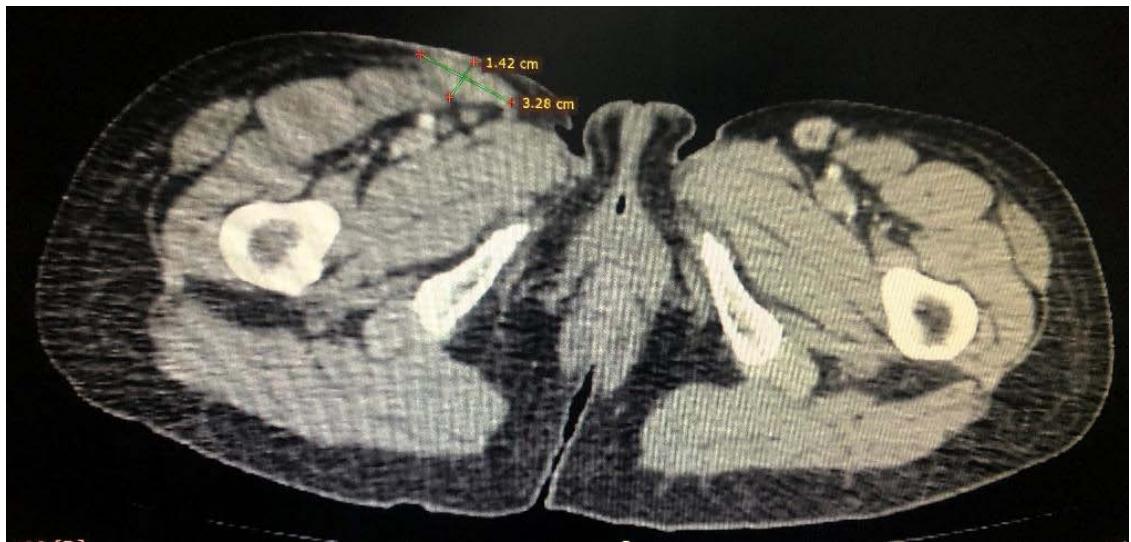

Computed tomography of the chest showed the presence of confluent lymphadenomegaly in the right axillary chain, forming a mass with a center of necrotic, measuring approximately $56 \times 40 \mathrm{~mm}$ in their largest diameters. Other non-confluent lymph nodes of increased size were observed in the ipsilateral axillary chain, left axillary chain and retroperitoneum. Abdominal CT scans showed prominent lymph nodes in the common iliac chain and bilateral inguinal nodes.

C Fig. 3: (A) CT scan of the right axillary region showing confluent lymph nodes forming a mass with a necrotic center measuring approximately $56 \times 40 \mathrm{~mm}$ in its largest diameters; (B and C) CT scan showing lymphadenopathy in chains in the right inguinal region and the right common iliac region respectively.